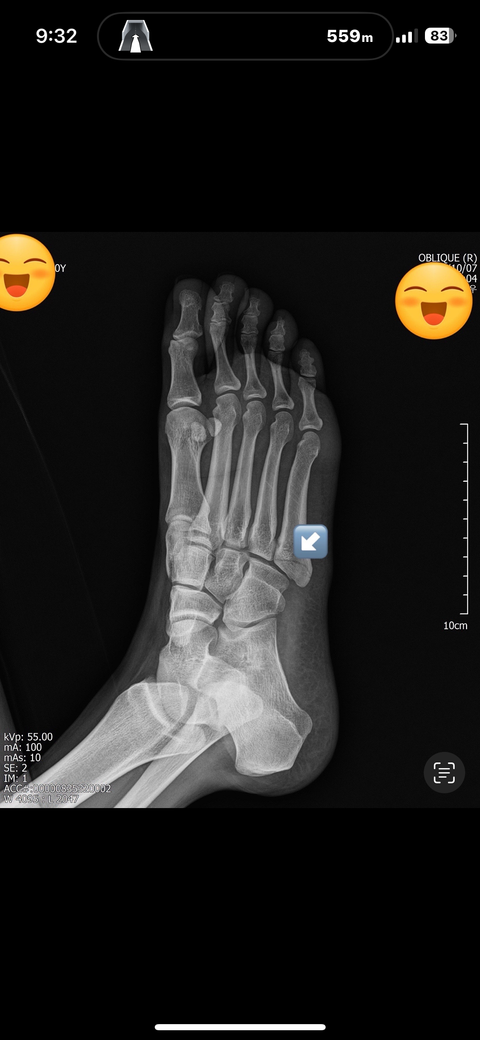

5중족골 골절 수술과비수술 봐주세요

10/5접지름으로인한 5중족골 기저부골절